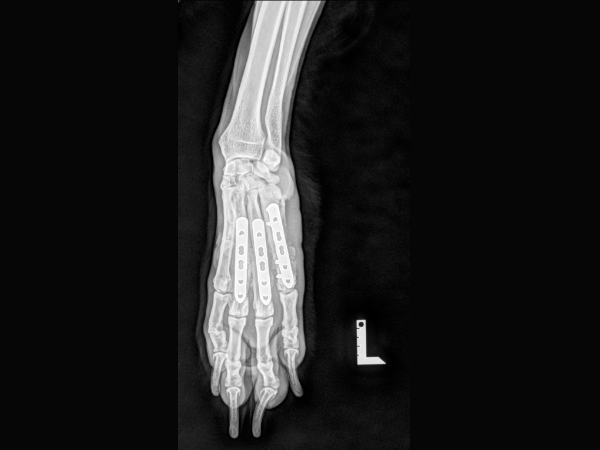

<術後のレントゲン>

インプラントによる内固定を行いました。

▼術後